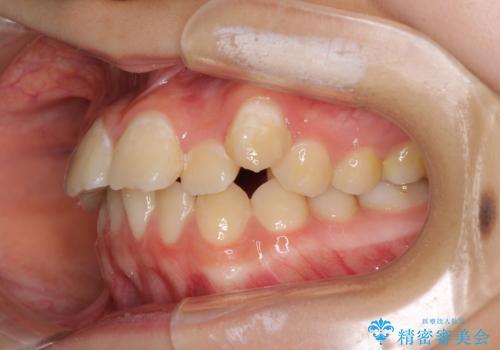

- 目立つ八重歯を改善したいとのことで来院された患者様です。

奥歯の咬み合わせは左右とも理想的なものでしたが、下顎前歯が1本欠損しているため、上下のバランスを保つことが難しい歯列でした。

唇を閉じたときに上顎前歯が下顎の唇に乗っかる印象があったため、八重歯の後方にある小臼歯を1本抜歯することとしました。

変則的な抜歯となるため、臼歯の咬合が理想的でなくなることが懸念されますが、インビザラインにて矯正治療を行うこととしました。